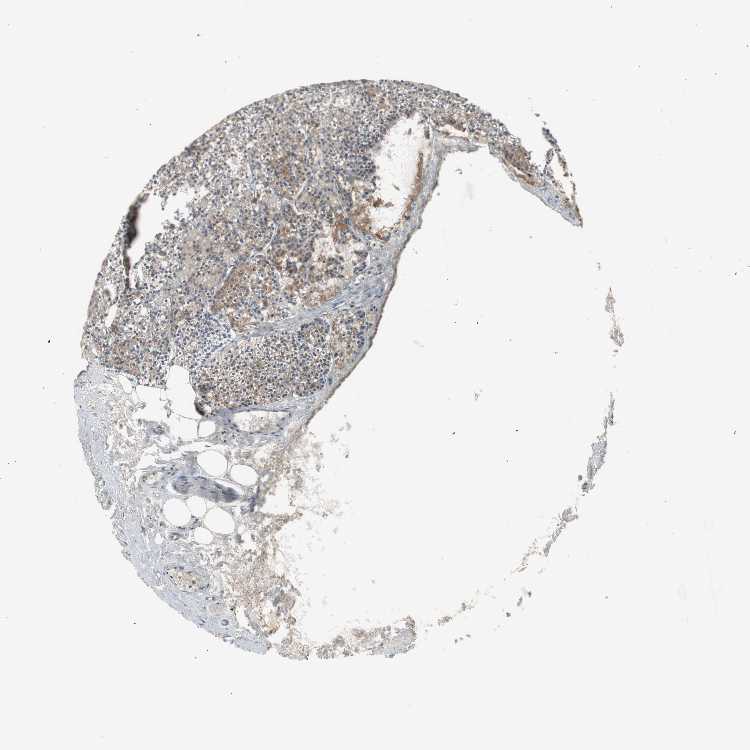

TISSUE PRIMARY DATA PARATHYROID GLAND Show tissue menu

PARATHYROID GLAND - Antibody stainingi

Antibody staining in the annotated cell types in the current human tissue is reported as not detected, low, medium, or high, based on conventional immunohistochemistry profiling in selected tissues. This score is based on the combination of the staining intensity and fraction of stained cells.

Each image is clickable and will lead to virtual microscopy that enables deeper exploration of all samples and also displays staining intensity scores, fraction scores and subcellular localization as well as patient and tissue information for each sample.

Antibody HPA006114Antibody HPA050659

Glandular cells MediumMedium